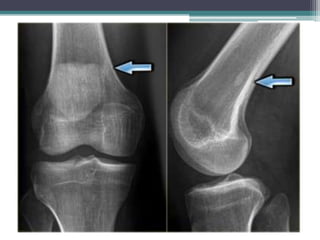

OSTEOSARCOMA Hechos ycifras • Tumor óseo maligno primario mas común. • Segundo tumor óseo primario más común y es altamente maligno. Es más común entre las personas de 10 a 25 años, aunque puede ocurrir a cualquier edad. • 50% alrededor de la rodilla (fémur distal con más frecuencia que la tibia proximal) o en otros huesos largos (como el húmero proximal), en particular en la zona metafiso diafisaria, y puede metastatizar, por lo general a los pulmones o en otros huesos. • Presentación: dolor, masa, fractura patológica. • La esclerosis está presente, ya sea en la formación de tumores de hueso nuevo o esclerosis reactiva.

• Las radiografíassimples típicamente revelan lesiones con patrón apolillado o permeativo de la zona de transición con destrucción cortical irregular y una reacción perióstica interrumpida con extensión de tejidos blandos. • Una reacción perióstica conocida como “triángulo de Codman” aparece cuando el tumor eleva el periostio del hueso subyacente. • La extensión cortical de tejido blando puede producir espículas radiadas de hueso llamado apariencia en “rayo de sol”.

• El osteosarcomamaligno produce osteoide (hueso inmaduro) de las células óseas tumorales. • La formación de hueso explica las imágenes radiográficas. • Cuando la matriz tumoral ósea es deficiente, el osteosarcoma puede ser del subtipo telangiectasico (que algunas veces puede imitar un quiste óseo aneurismático), o el diagnóstico diferencial incluye el sarcoma de Ewing o linfoma, especialmente cuando una gran masa de tejido blando está presente. • En pacientes de edad avanzada, el diagnóstico diferencial también puede ser condrosarcoma.

• Generalmente sedesarrolla alrededor de la rodilla • El dolor y la hinchazón son los síntomas habituales. • Los hallazgos en los estudios de imagen varían y pueden incluir características escleróticas y / o líticas. • El diagnóstico requiere una biopsia. • Se necesitan radiografías de tórax y TC para detectar metástasis pulmonares y una gammagrafía ósea para detectar metástasis óseas.

• El osteosarcomaintraóseo de bajo grado es una variante muy rara de osteosarcoma, que sin embargo puede tener un aspecto radiológico benigno y por lo tanto puede ser confundido con otras lesiones, por ejemplo, la displasia fibrosa. • Osteosarcomas superficiales tienen su origen en la superficie del hueso y crecen principalmente en los tejidos blandos circundantes, pero también puede infiltrarse en la médula ósea. Entre estos, el osteosarcoma parostal (o yuxtacorticales) es la variante más frecuente, más comúnmente en el lado posterior de la unión metafiso diafisaria distal del fémur.